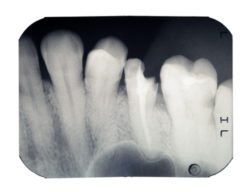

- True. Our teeth are coated in a layer of enamel that protects them from bacteria. When a tooth is damaged, bacteria can then bypass the enamel, reaching the inner layers of dentin and causing decay and/or infection. Patients then experience minor to serious discomfort, including tooth sensitivity and toothaches.

- True. If a tooth is broken or fractured, we can repair it with a crown. The crown act as a cap, fitting over the entire visible portion of the tooth. We use ceramic to ensure the restoration looks natural and blends with the smile.